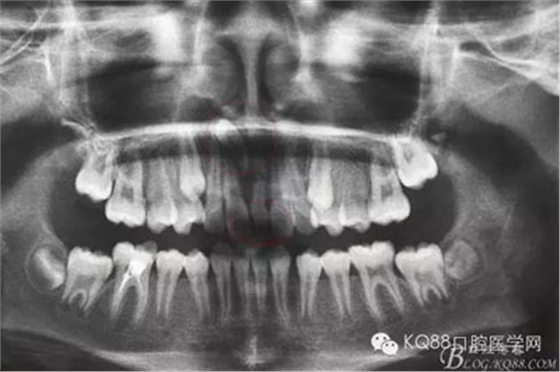

圖2.術(shù)前全景片檢查:除了已經(jīng)萌出的一枚多生牙外,在11根尖上方有一倒置多生牙,牙冠與鼻腔相通,牙根位于11和萌出的多生牙之間。